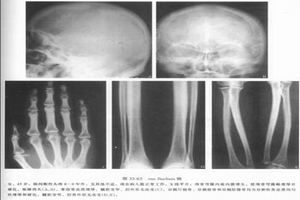

3.X線檢查

(1)長管骨:骨內、外骨膜骨化而附加於原皮質表層,致使骨皮質增厚、硬化,以骨幹中段顯著,髓腔狹窄或完全消失,但可有斑片狀密度減低區,可見骨周圍軟組織萎縮。受累骨骼的發生頻率依次為脛骨、股骨、肱骨、尺骨、橈骨和腓骨。典型者為對稱分布,通常乾骺受累較輕,偶爾累及骨骺。

(2)短管骨:跖骨常受累,病變較輕,其病變形態與長骨相似,皮質增厚,骨幹增粗,雙側病變基本對稱。

(3)顱骨:顱蓋骨肥厚,主要為內、外板增厚硬化或板障狹窄、消失、顱底骨硬化、顱底神經和血管通過的孔道狹窄。

(4)其他骨骼:個別可見脊柱椎板較緻密,亦可累及肋骨、鎖骨及骨盆。病變的主要表現是皮質骨增厚、硬化。

X線檢查顯示,病變以四肢長骨、顱骨多見,亦可累及掌骨、肋骨、肩胛骨、鎖骨和脊柱。長骨內外膜增厚、骨皮質緻密或呈層狀,骨幹梭形增粗,表面不平,骨髓腔變窄。但病變不累及骨骺、乾骺端及關節面。顱骨內外板增厚,密度增高,有不規則硬化斑,以顱底為明顯。脊椎可有灶性斑片狀硬化影。